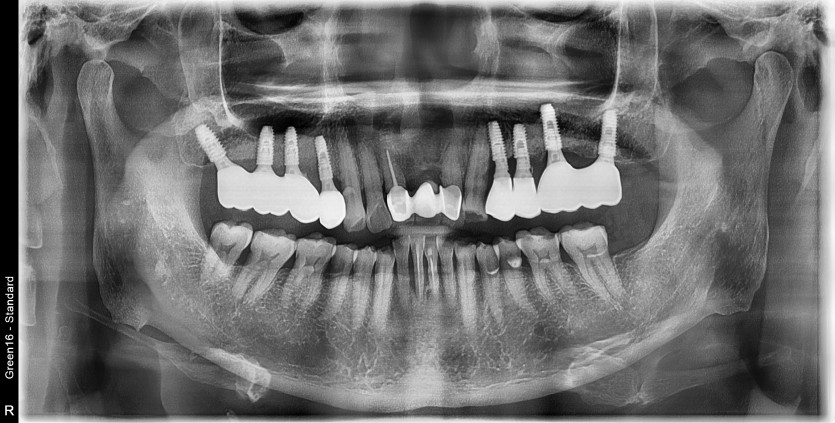

#24.25 타원임플란트 제거 후

임플란트 재수술 + 치조골 이식술 시행하였습니다.